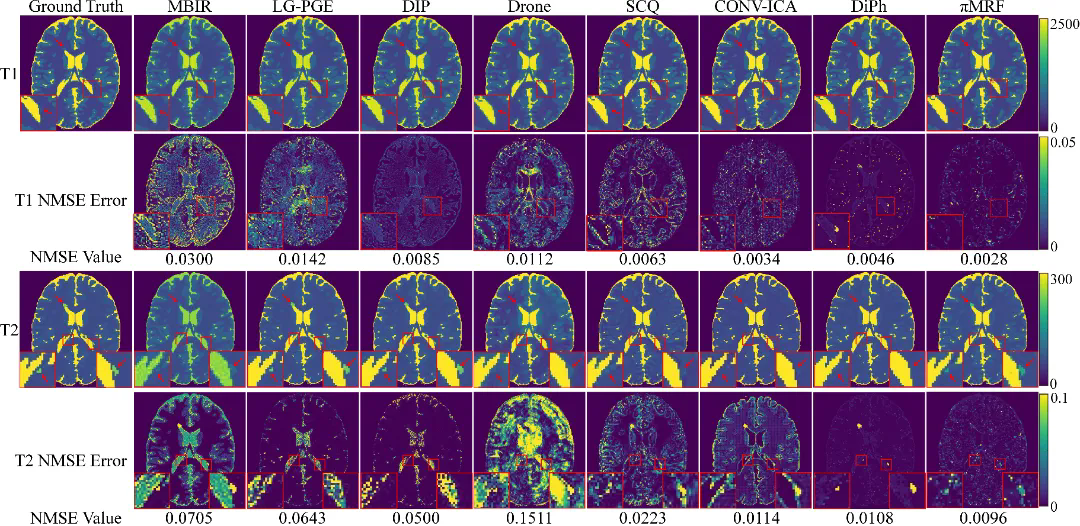

在數(shù)字仿真、水模仿體以及在體人腦實驗中,πMRF在極端欠采樣條件下均表現(xiàn)出更高的定量準確性與空間一致性,能夠穩(wěn)定恢復T1、T2和PD參數(shù)分布,并在組織邊界及病灶區(qū)域保持更可靠的細節(jié)表達,整體性能顯著優(yōu)于現(xiàn)有對比方法。上述結(jié)果表明,該研究有效緩解了 MRF 在極端欠采樣條件下面臨的不適定逆問題,展示了“物理模型與連續(xù)神經(jīng)表示深度融合”在復雜醫(yī)學成像反演任務中的應用潛力。

圖3:數(shù)字仿真實驗結(jié)果